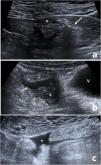

Classification of acute diverticulitis in the left colon with ultrasonography and computed tomography: Value of current severity classification schemes

The current management of acute diverticulitis of the left colon (ADLC) requires tests with high prognostic value. This paper analyzes the usefulness of ultrasonography (US) in the initial diagnosis of ADLC and the validity of current classifications schemes for ADLC.

This retrospective observational study included patients with ADLC scheduled to undergo US or computed tomography (CT) following a clinical algorithm. According to the imaging findings, ADLC was classified as mild, locally complicated, or complicated. We analyzed the efficacy of US in the initial diagnosis and the reasons why CT was used as the first-line technique. We compared the findings with published classifications schemes for ADLC.

A total of 311 patients were diagnosed with acute diverticulitis; 183 had ADLC, classified at imaging as mild in 104, locally complicated in 60, and complicated in 19. The diagnosis was reached by US alone in 98 patients, by CT alone in 77, and by combined US and CT in 8. The main reasons for using CT as the first-line technique were the radiologist’s lack of experience in abdominal US and the unavailability of a radiologists on call. Six patients diagnosed by US were reexamined by CT, but the classification changed in only three. None of the published classification schemes included all the imaging findings.

US should be the first-line imaging technique in patients with suspected ADLC. Various laboratory and imaging findings are useful in establishing the prognosis of ADLC. New schemes to classify the severity of ADLC are necessary to ensure optimal clinical decision making.